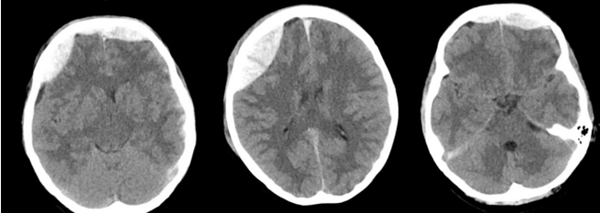

近日,中山大学附属第一医院(简称中山一院)广西医院神经外科团队成功救治一名因外伤导致迟发性硬膜外血肿的患者,经开颅硬膜外血肿清除术后,患者最终康复出院,并为科室送来一面写有“医术精湛挽危厄,仁心厚德臻至善”字样的锦旗,表达对科室全体医护人员感谢。患者黄女士(化名)是一名警员。因意外受伤被送到捆绑调教 急诊科救治。捆绑调教 立即启动绿色通道,为患者进行全面检查,头颅CT提示,额骨、右顶骨有20...